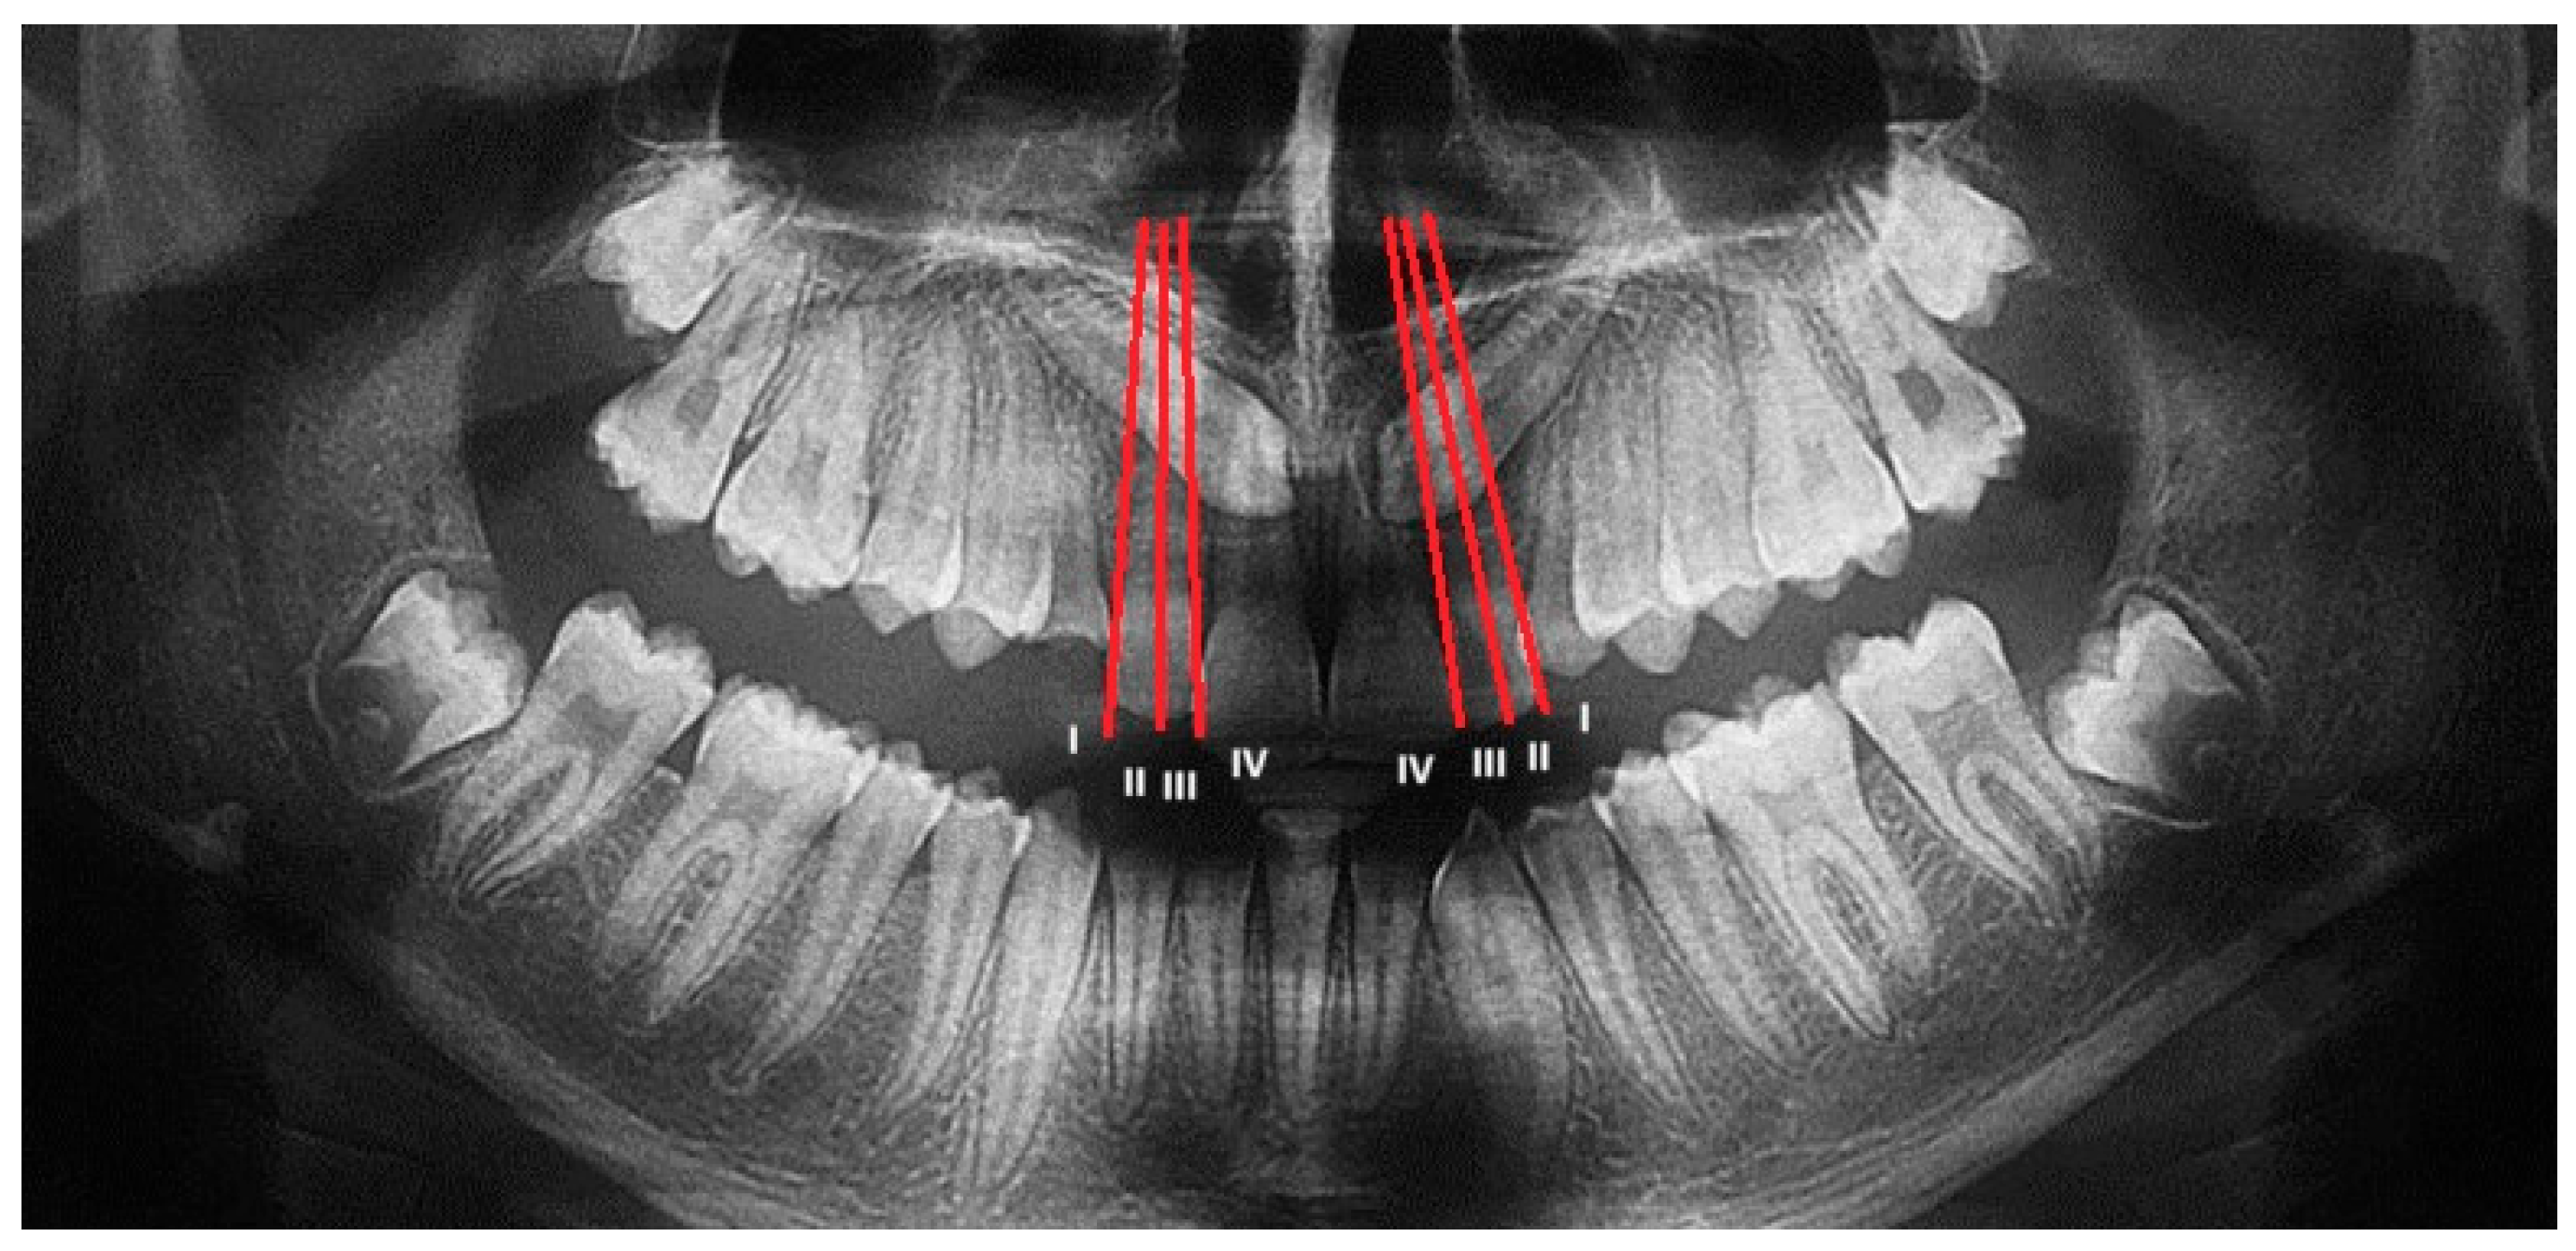

The Lindauer [2] sector division was considered to evaluate the mesio-distal position of canines’ cusps. The authors described four sectors, listed in order of severity of prognosis:

Sector I: area distal to the line tangent to the distal surface of the lateral incisor;

Sector II: area mesial to sector I, distal to the line that divides the mesiodistal surface of the lateral incisor along its major axis;

Sector III: area mesial to sector II, distal to the line tangent to the mesial surface of the lateral incisor;

Sector IV: includes the area mesial to Sector III (Figure 2).

Figure 2.

Sector of inclusion measured on OPT according to Lindauer. Both maxillary canines are included in sector IV.